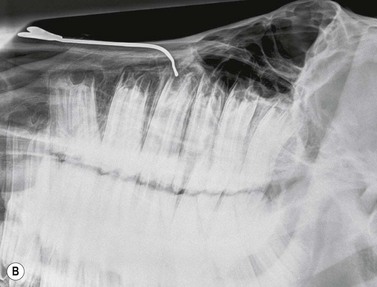

Fig. 13.20 (A) Intra-oral radiograph of a maxillary cheek teeth row.

Radiograph courtesy of J. Easley.

image

(B) Intra-oral radiograph taken intra-operatively during a dental extraction procedure. A small bone-opacity fragment can be seen in the rostral aspect of the alveolus (arrow).

(Radiograph courtesy of W.H. Tremaine.)

The use of human dental film packs4 or of improvised cassettes made of vinyl7 or heavy-duty black polythene1 has been described for intra-oral projections in horses. Pre-packed human dental film is often only large enough to image one or two cheek teeth on each radiograph, and this is a major disadvantage, particularly because the affected tooth is not commonly identified prior to the radiographic examination. Improvised cassettes can be made into a suitable shape for the equine oral cavity (circa 10 × 25 cm) by cutting down film and card-mounted intensifying screen(s) before double wrapping them in closely fitting, light-proof bags e.g., of heavy-duty black polythene, and sealing the edges with light-proof adhesive tape.1 The disadvantages of this system include the time taken to prepare the above materials, poor film/screen contact and the need for wet processing of films.

A self-retaining, full-mouth speculum is used to open the mouth of the heavily sedated or anesthetized horse, and the film is placed in the oral cavity, parallel to the hard palate (Fig. 13.19). If using a small sized film, it must be placed at the level of the tooth of interest. For teeth of mature or older horses, the X-ray beam is directed at an angle of 50°–60° to the horizontal, but to examine the longer reserve crowns of young horses, increased incident angles (70°–80°) are required (Fig. 13.19). The centering point is somewhere between the level of the facial crest and up to 6 cm dorsal to the facial crest, depending on the length of the tooth being radiographed i.e., in younger horses, a more dorsal centering point is required compared to aged horses with short reserve crowns.